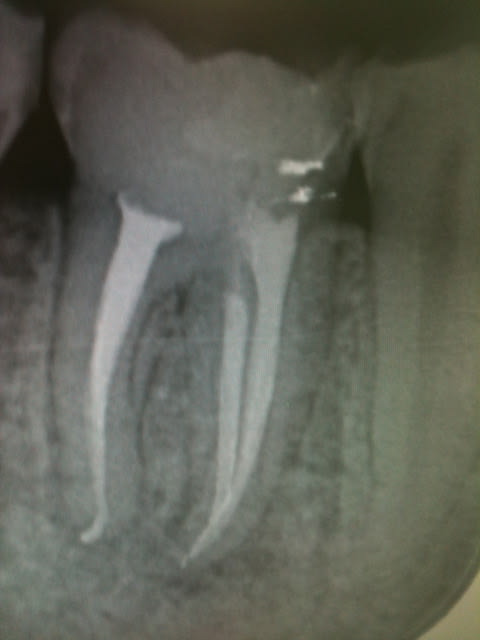

La double courbure en distal m'as donné du mal!

Endo2 a0utav - Eugenol

Pas de soucis particulier mais arthrite post op. Je crois que je vais me régler à 1 mm de l'apex radiologique désormais.

Ben oui, parce là, tu défonces le foramen à chaque fois. Sers-toi du localisateur et respecte ses indications.

Ca n'arrive pas à chaque fois. Comme ca c'est mieux ?

Un peu. Tu as tendance à ne pas savoir te retenir. Un obturateur précoce, en quelque sorte.

bon j'arrete le r40, une étape en moins

R46 kgfurh - Eugenol

Et dans la foulée comme j'étais en forme.....

R49 ucxpkp - Eugenol

Tu fais comment ton obturation ? Lentulo pâte et monocone ?

Pas de lentulo. Scellement monocone ah+. Effectivement c'est le seul moment ou sur une dent mandibulaire la salive peut faire chier car j'enlève le lingua-fix pour la radio (optragate toujours en place).

D'un autre coté comme le résultat est reproductible il est rare de retirer les cones et de réinstrumenter.